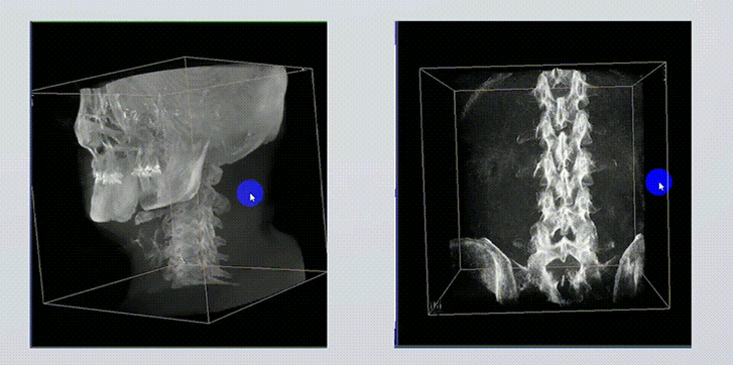

1、術(shù)中實(shí)時(shí)三維成像

術(shù)中三維成像和橫斷面圖像提供多角度的手術(shù)診斷信息,輔助醫生進(jìn)行術(shù)中評估判斷,諸如骨折復位情況和內植入螺釘的尺寸和位置,輔助手術(shù)更好地完成。

2、三維成像視野大

提供更大的術(shù)中三維成像視野,采集更多圖像信息,可一次拍全全段頸椎、全段腰椎、七節胸椎、雙側骶髂關(guān)節、股骨頭及單側盆骨。